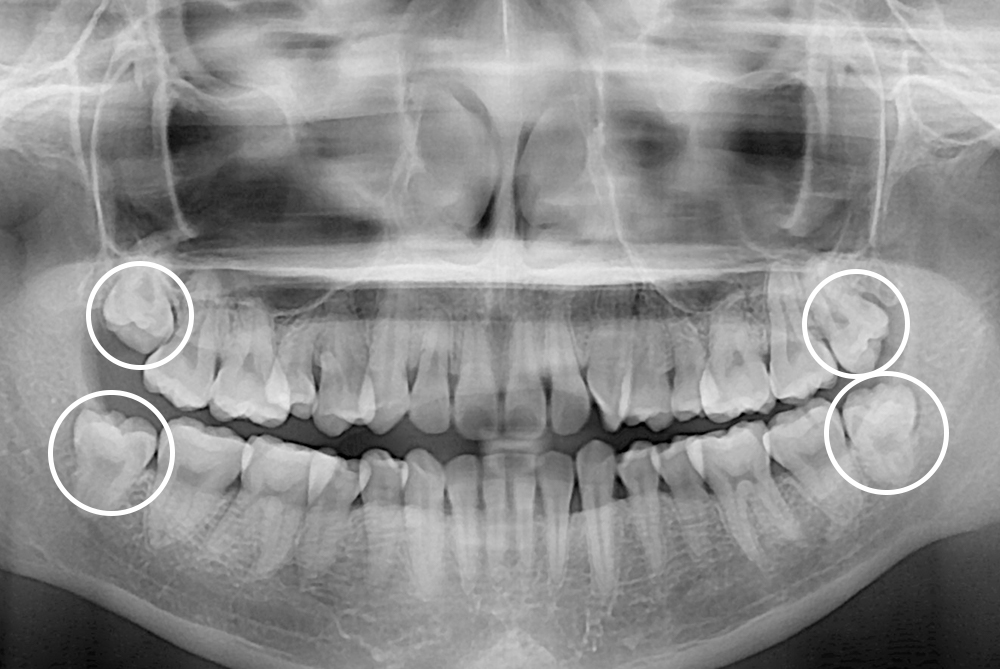

[사랑니] 매복 사랑니 발치

치료후 : 2018-06-18

세종치과는 구강악안면외과학 박사이신 원장님이 발치하는 치과입니다.